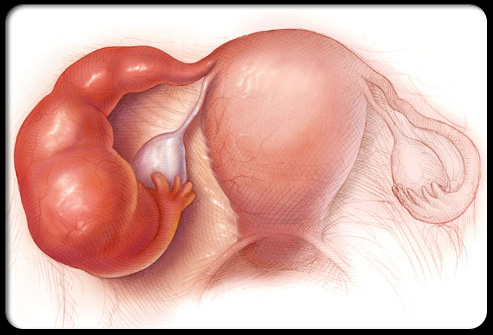

异位妊娠(宫外孕)

盆腔疼痛怎么引起的,盆腔疼痛是什么原因引起的

宫外孕指胚胎在子宫外着床发育,会导致尖锐的盆腔疼痛,通常出现在身体一侧,并可能伴有阴道出血、恶心和晕眩。宫外孕如果发现得足够早,是可以通过药物治疗的,但是如果出血或输卵管破裂,那么需要紧急手术治疗。